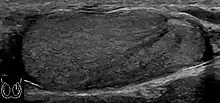

However, these patterns, except the latter one, may be considered as non-specific as heterogeneous echotexture and shadowing calcification can also be detected in malignant testicular tumors. The onion peel pattern of epidermoid cyst [Fig. 10] correlates well with the pathologic finding of multiple layers of keratin debris produced by the lining of the epidermoid cyst. This sonographic appearance should be considered characteristic of an epidermoid cyst and corresponds to the natural evolution of the cyst. Absence of vascular flow is another important feature that is helpful in differentiation of epidermoid cyst from other solid intratesticular lesions.